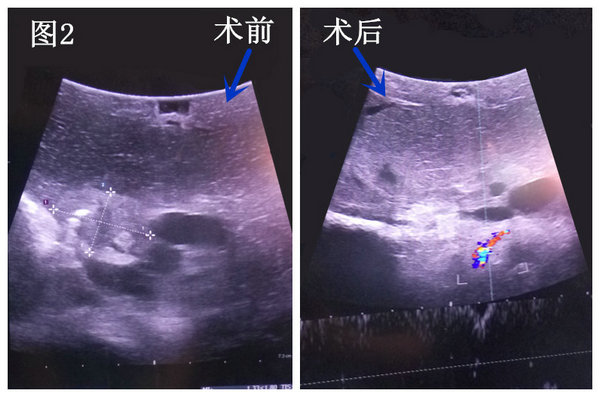

手术于2016年2月29日如期进行,该手术由李晓勇教授亲自主刀,杨战锋主治医师及张永医师参与手术。术中,超声诊断科杨青主任利用彩超进行精准定位,李晓勇教授依据电脑程序规划、设计布针路线,精准的将多根电极针分别植入肿瘤组织,实时监控肿瘤消融的范围及程度。电击开始后,1500伏高压脉冲瞬间贯穿病灶,击穿癌细胞。术后彩超提示肿瘤彻底消融(图2),未损伤胆管及血管。同时行T型管引流解决胆道梗阻问题。麻醉科胡强夫主任及杨楠护士长带领的医护团队在术中积极配合,确保了手术成功完成。术后,在主管医师杨战锋及宋伟华护士长的精心治疗和护理下,患者目前恢复顺利。